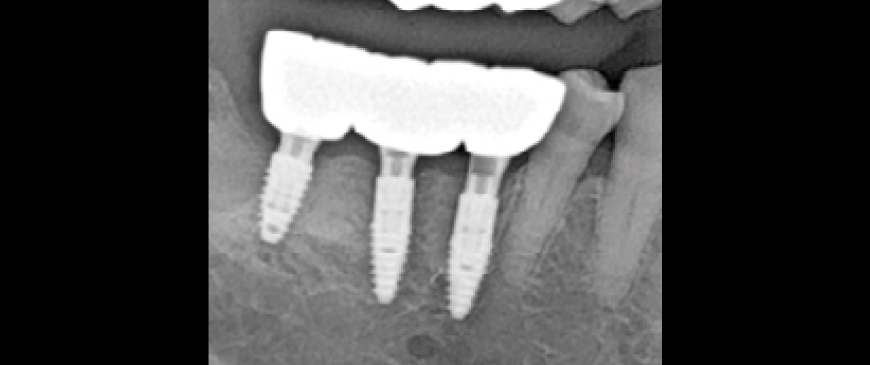

Fig 11

Intraoral Clinical Images, Radiographs, and CBCT Scans at Three Months After Loading Although this represents a relatively short follow-up period, the clinical and radiographic evaluation at three months post-loading showed comparable outcomes to conventional Blue Diamond (BD) implant cases, demonstrating no signs of compromise in stability or bone response.